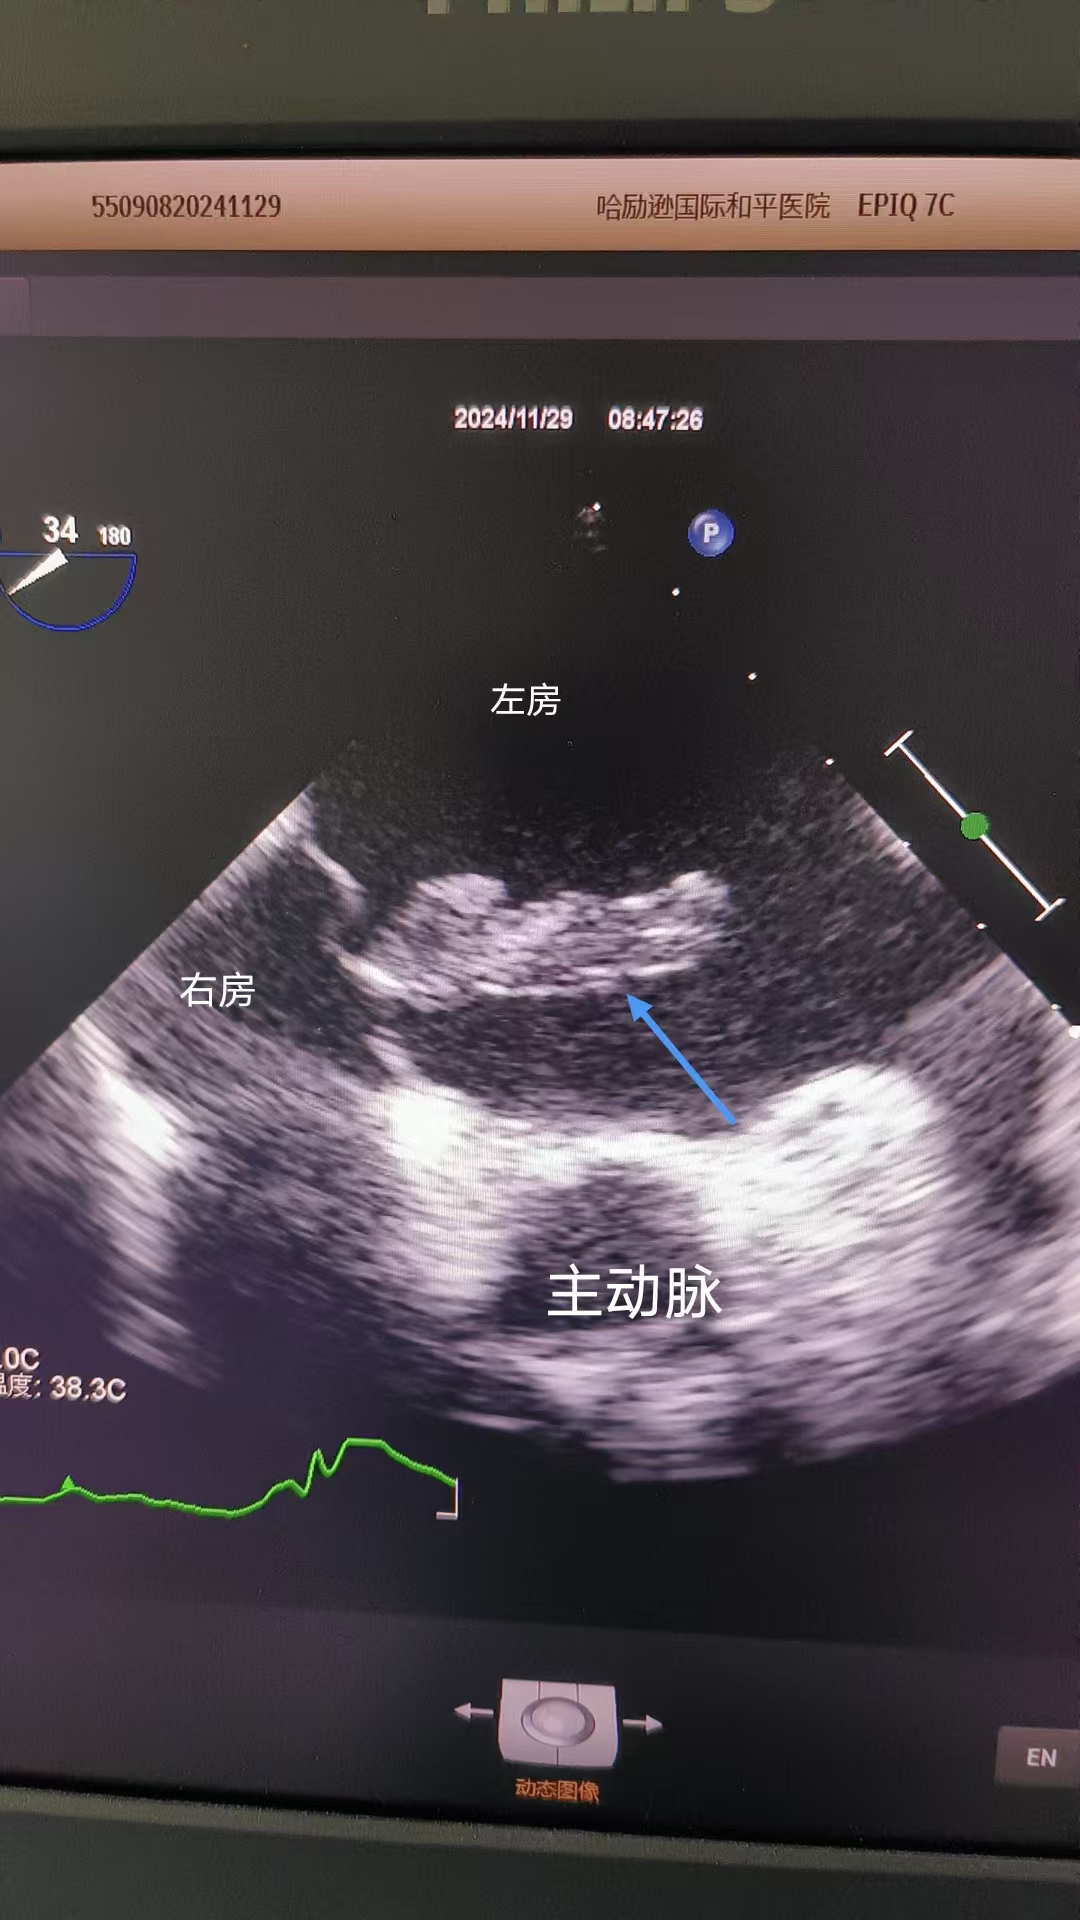

同声相应,同气相求。孙霞、李琳等作为此次无痛经食道超声心动图检查MDT小组的专家,为此项开先河的检查提供了坚强技术后盾。姚阿姨的家人了解情况后,也放下心来。在孙霞的指导下,秦丽娴熟地将直径仅几毫米的探头经口腔轻柔、精准进入患者食道,转动探头,从0°到180°的视觉,来检查心脏的各个腔室、各瓣膜的情况,对心脏左房内团块进行全方位评估,通过其在左房的位置、活动度、回声、肿物蒂的情况等,最后考虑为左房粘液瘤。检查结束后,姚阿姨感慨万分:“本以为会很难受,没想到睡一觉就结束了,醒来也没有不舒服,高科技真是神奇!”

高清晰度的无痛经食道超声心动图检查影像报告。